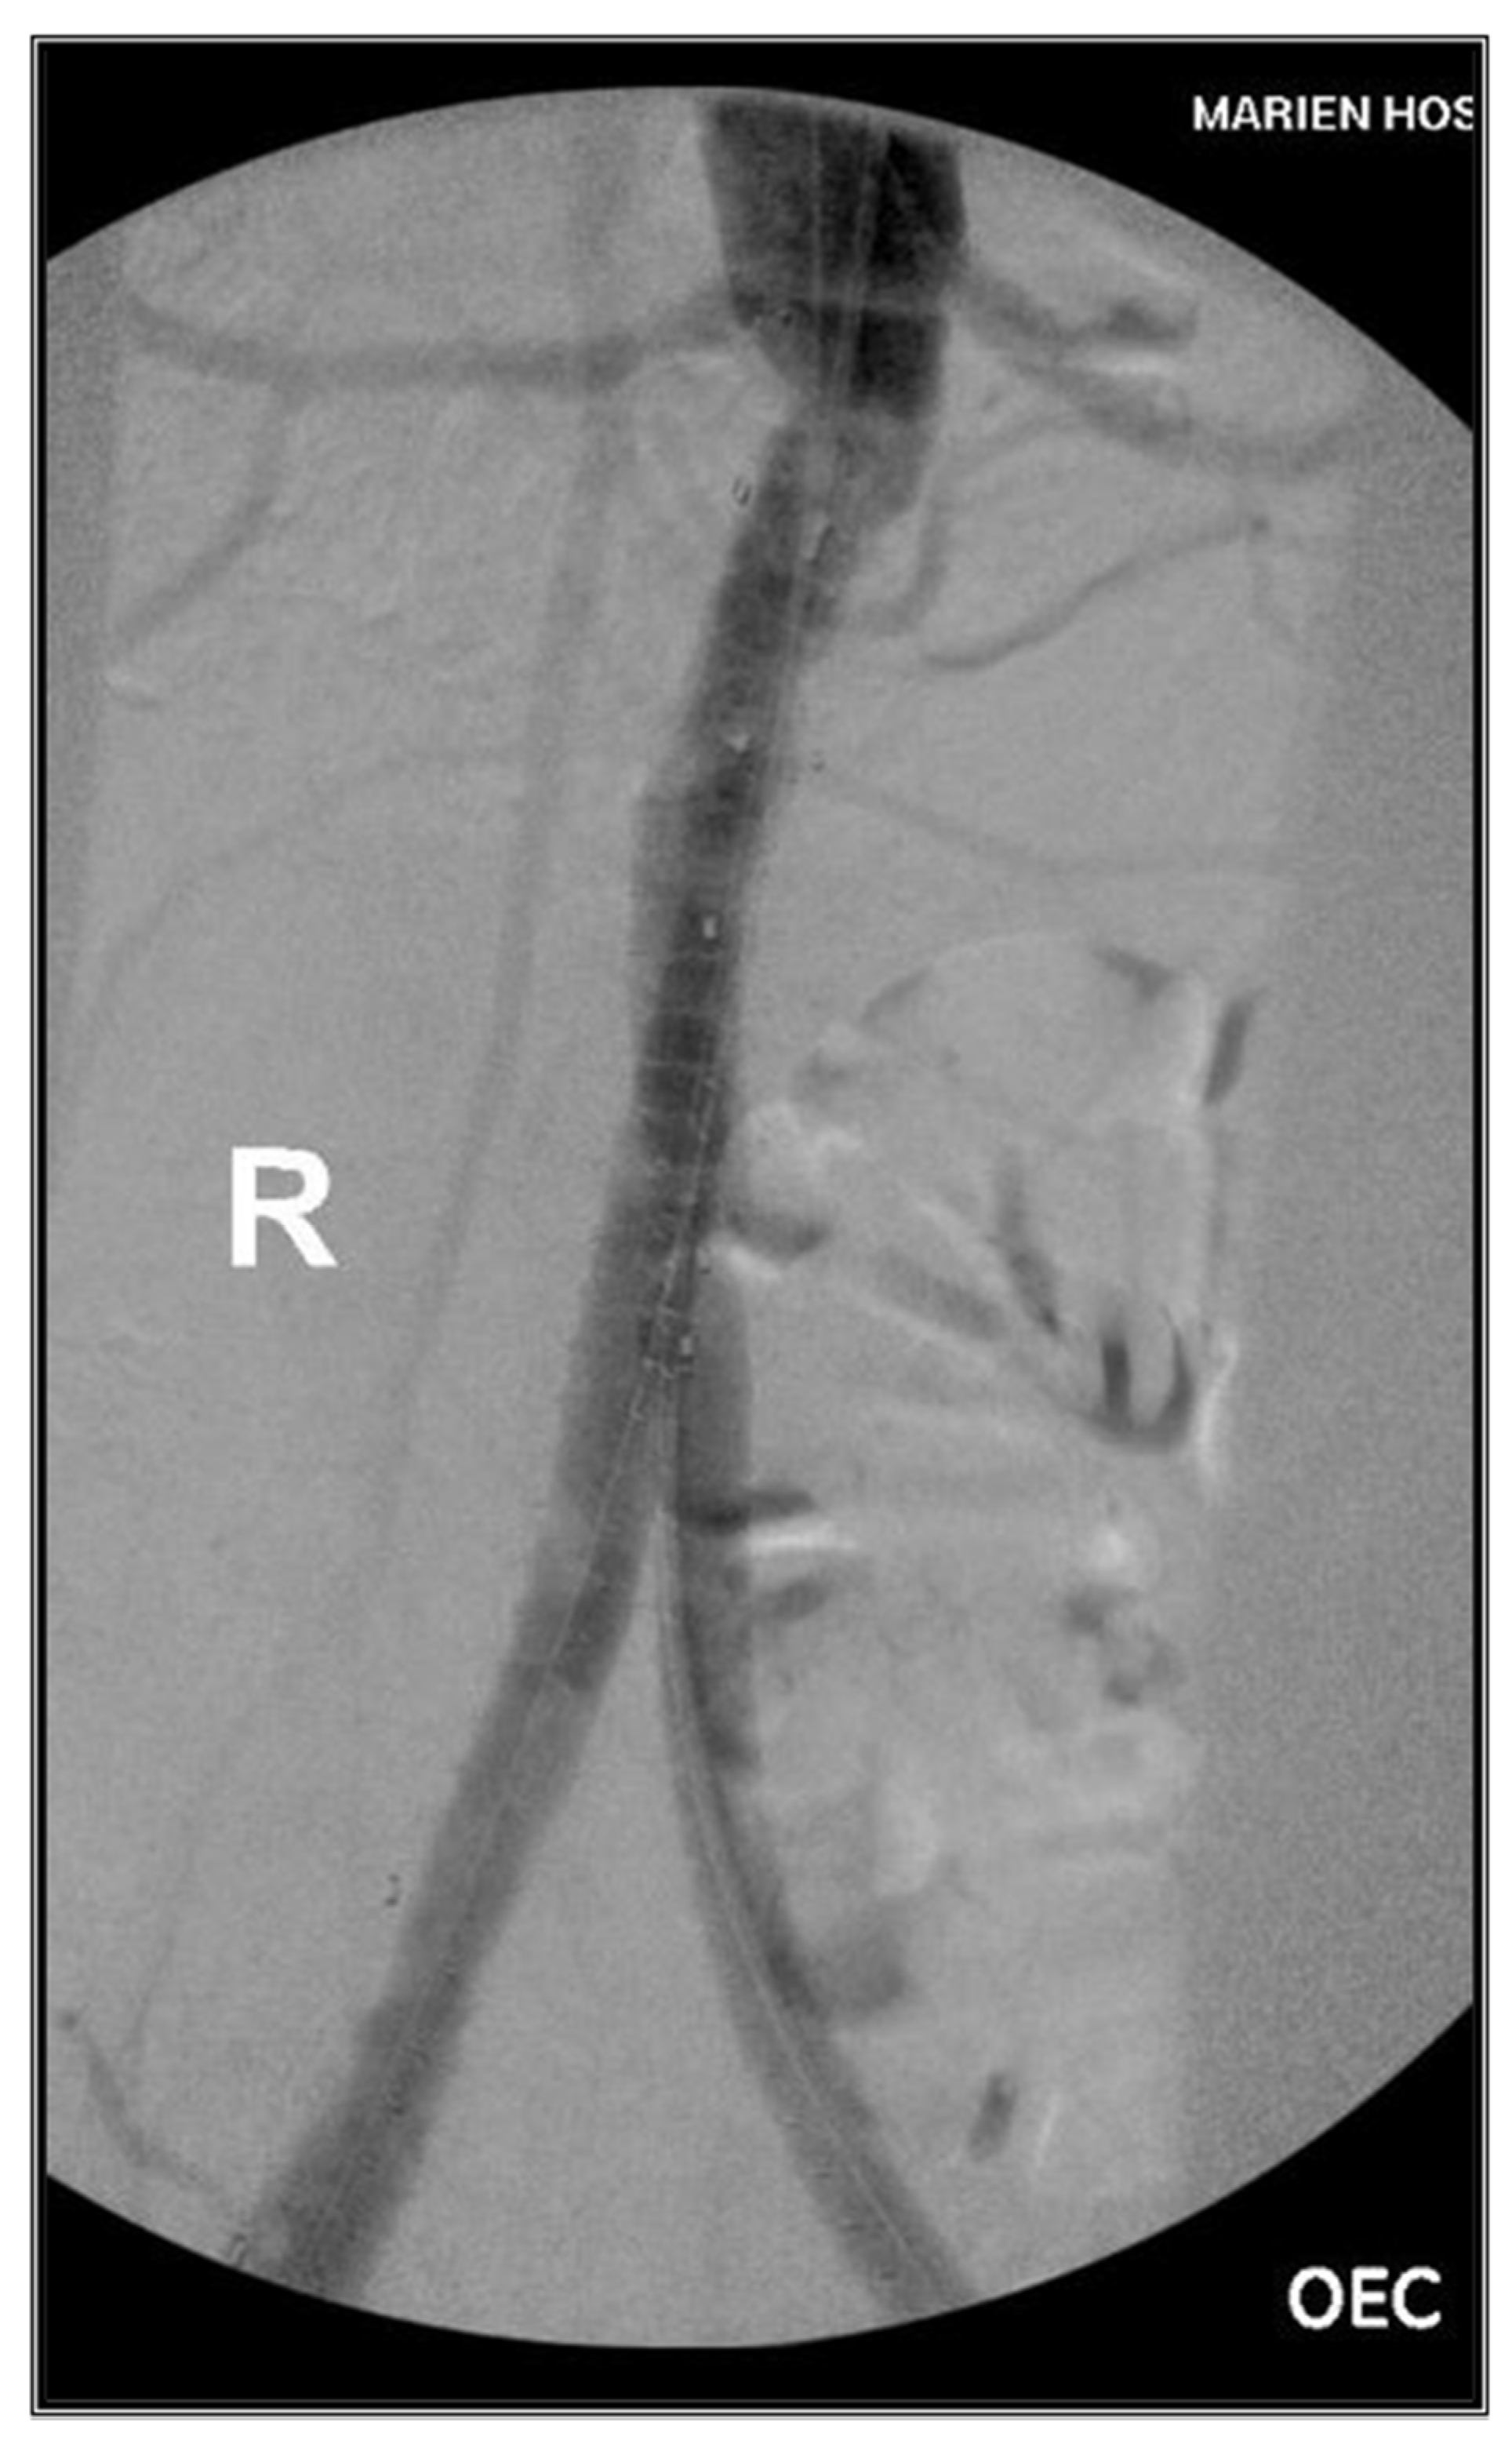

3.2. Case II